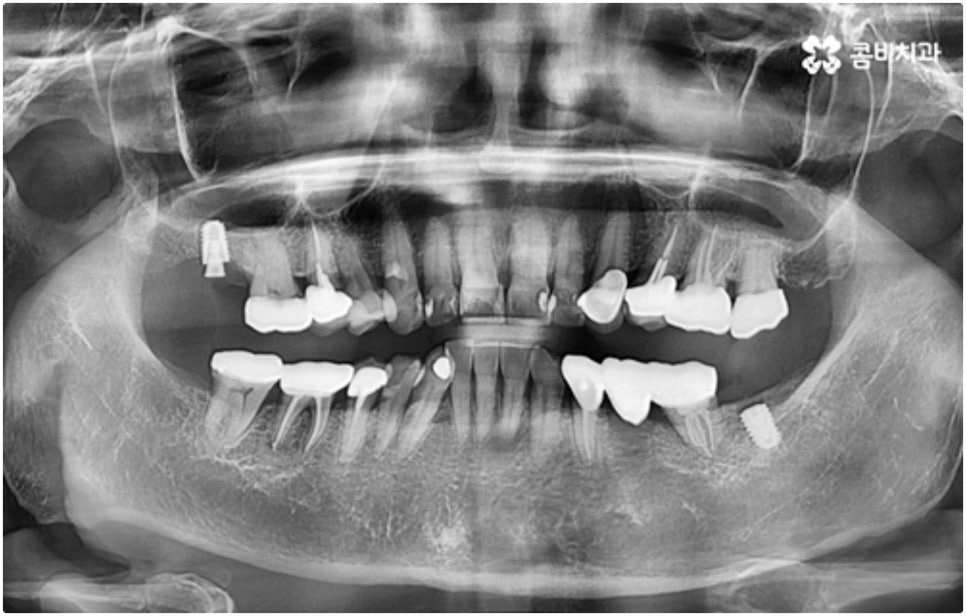

임플란트 시술이 환자분들의 잇몸뼈에 직접 고정을 시키는 방법인 만큼 개개인의 치주 상태, 구강 내부 구조 등을 면밀하게 살펴보고 치료 계획을 세워야 하며 그 밖에도 치아가 빠진 지 얼마의 시간이 흘렀는지, 장기적으로 복용 중인 약이 있는지 등 영향을 줄 수 있는 모든 관련 상황을 종합적으로 고려하여 환자분들에게 딱 맞는 어금니임플란트 시술을 무리하지 않게 진행하는 것이 중요한 체크 포인트라고 할 수 있는데요. 그렇기 때문에 먼저 3D CT를 이용한 정밀한 검사를 통해 어떤 종류의 임플란트를 어떻게 진행할지 신중하게 검토해야 하며 또한 풍부한 노하우와 뛰어난 기술력을 갖추고 있는 의료진과 함께 충분한 사전 상담을 하실 필요가 있습니다.

하루 빨리 불편함을 덜고자 하는 마음에 전체 어금니임플란트 시술 기간이 얼마나 되는지 문의주시는 분들이 많이 있는데요. 보통 임플란트 시술은 3~6개월 정도 걸리지만 환자분들의 상황에 따라서 어금니임플란트 시술을 받기 전에 다른 치료를 먼저 해 줄 필요가 있다면 8개월 넘게 걸릴 수도 있어요.

식립 성공률 및 지속적인 안정성을 높이기 위해서는 초기 고정이 잘 이루어져야 하는데 만약에 식립 바탕이 되는 잇몸뼈의 상황이 좋지 않다면 이와 관련된 치료를 먼저 해 줘야 하는 거예요. 예를 들어 치주 질환이 심하다면 이를 깨끗하게 치료해 주는 것이 우선시 되어야 하고, 잇몸뼈의 높이나 밀도 등이 부족한 경우에는 뼈이식 과정을 통해 이를 먼저 보충해 줄 필요가 있어요. 또한 윗어금니가 빠진지 오랜 시간이 지나 이미 골흡수가 일어나고 상악동이 많이 내려와 있다면 상악동 거상술 및 뼈이식을 한 후 임플란트 식립을 진행해야 할 거예요.